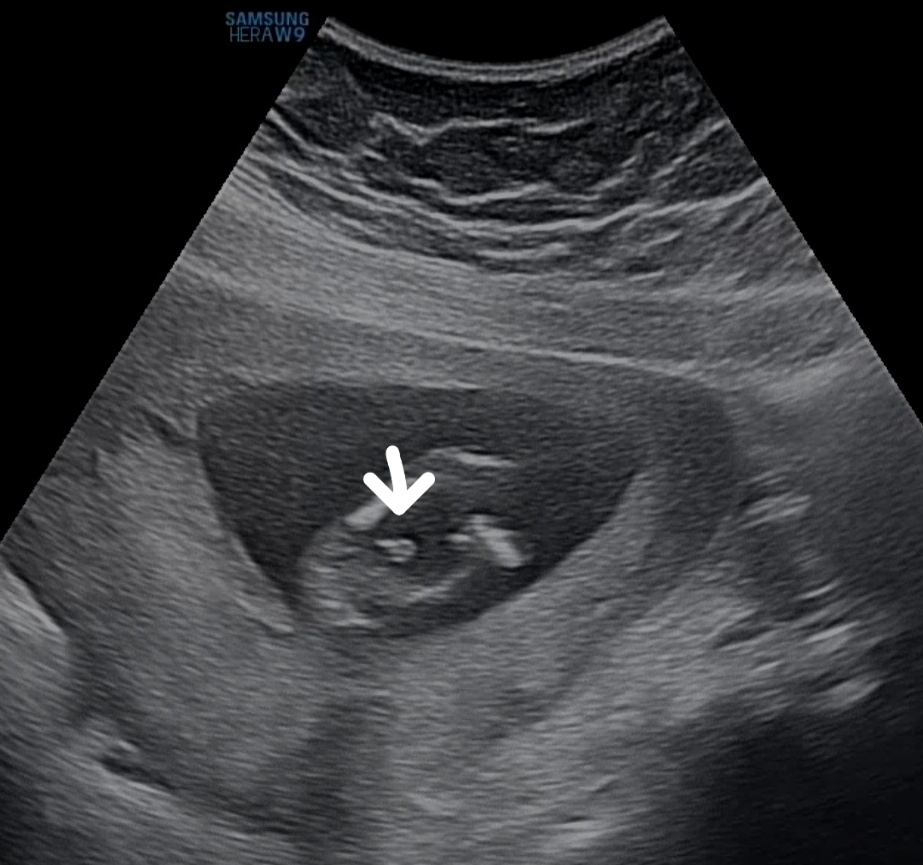

14주차예요 누가봐도 아들이죠..?ㅋㅋㅋ반전은없겠죠?

몇몇분은 또 모른다고 16주까지 기다려보라는데 제가봤을땐 너무 잘보여서욬ㅋㅋㅋㅋ 의사샘도 그런것같다곸ㅋㅋ(성별빨리안알려주시기로유명..ㅋㅋ) 반전은 없겠죠..ㅋㅋㅋ아들맘님들..